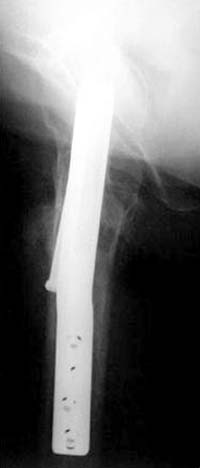

Правильная техника фиксации - это три параллельных  каннюлированных винта под углом 130 -135 градусов к диафизу, не ниже уровня малого вертеля. Проведенные ниже вертела винты с бОльшим углом (более вертикальные) в 20% осложнялись подвертельными переломами бедра. Ближе к кортикальному слою винты с длинным контактом резбовой части, а также каннюлирванные механически лучше, чем сплошные. Расположение винтово - в  в виде V т.е. один внизу по калькару и два сверху-спереди и сзади.

Вложение не в текстовом формате было извлечено…

Имя     : 4 Fem neck final ap.jpg

Тип     : image/jpg

Размер  : 26254 байтов

Описание: отсутствует

Url     : http://weborto.net:8080/pipermail/ortho/attachments/20120118/c4b77b39/attachment-0008.jpg